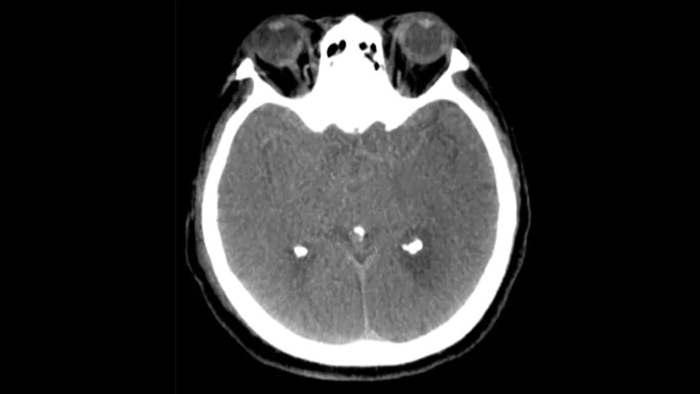

Visualização semelhante a TC

O SmartCT Soft Tissue  gera uma visualização tipo TC dos tecidos moles e suporta o diagnóstico de acidentes vasculares cerebrais de três formas. Um exame sem contraste ajuda na deteção de alterações isquémicas precoces. Um exame de fase precoce ajuda a identificar a oclusão proximal. Um exame melhorado de contraste de fase tardia suporta a deteção de colaterais.

SmartCT SoftTissue

Utilize imagens SmartCT SoftTissue (tipo TC) no conjunto Neurovascular para verificar o sucesso do tratamento e a existência de hemorragias.